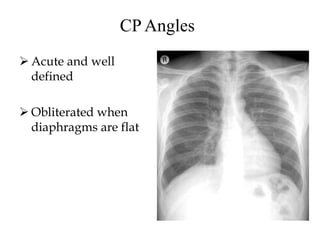

CP Angles

 Acute and well

defined

 Obliterated when

diaphragms are flat

CP Angles  Acuteand well defined  Obliterated when diaphragms are flat